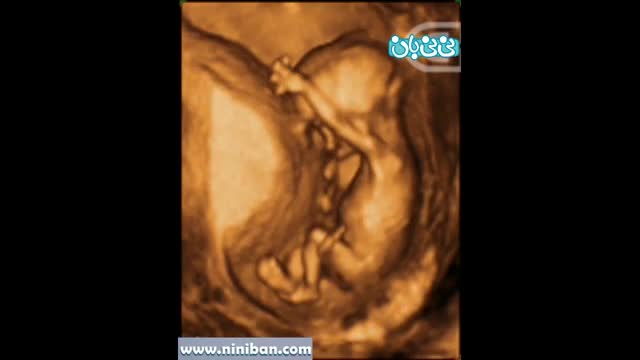

سونوگرافی چهار بعدی در بارداری هفته چهاردهم

۴ سال پیش

145233 بازدید